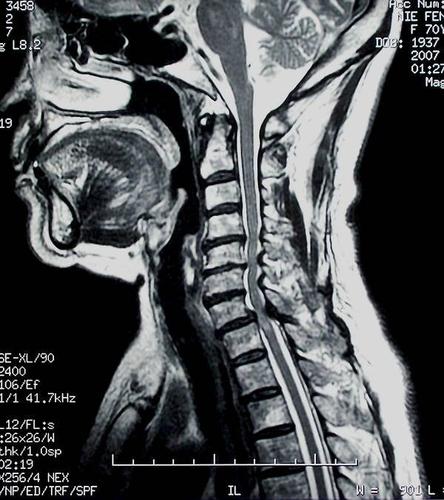

颈椎病核磁共振图解

颈椎病核磁共振图解,颈椎核磁片图解教程

颈椎核磁片图解教程

正常颈椎核磁共振图片

颈椎核磁共振图片图解

颈椎核磁共振

核磁共振图解

核磁共振图片

核磁共振片子

颈椎病片子